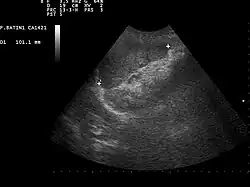

![]() Ultrasound image of a normal spleen that may be seen in part of the eFAST | |

- Left upper quadrant of the abdomen (perisplenic view). Left upper quadrant is examined by working your probe down the midaxillary line starting at the left 8th rib to the 11th rib. This examines for free fluid around the kidney and spleen. [15]